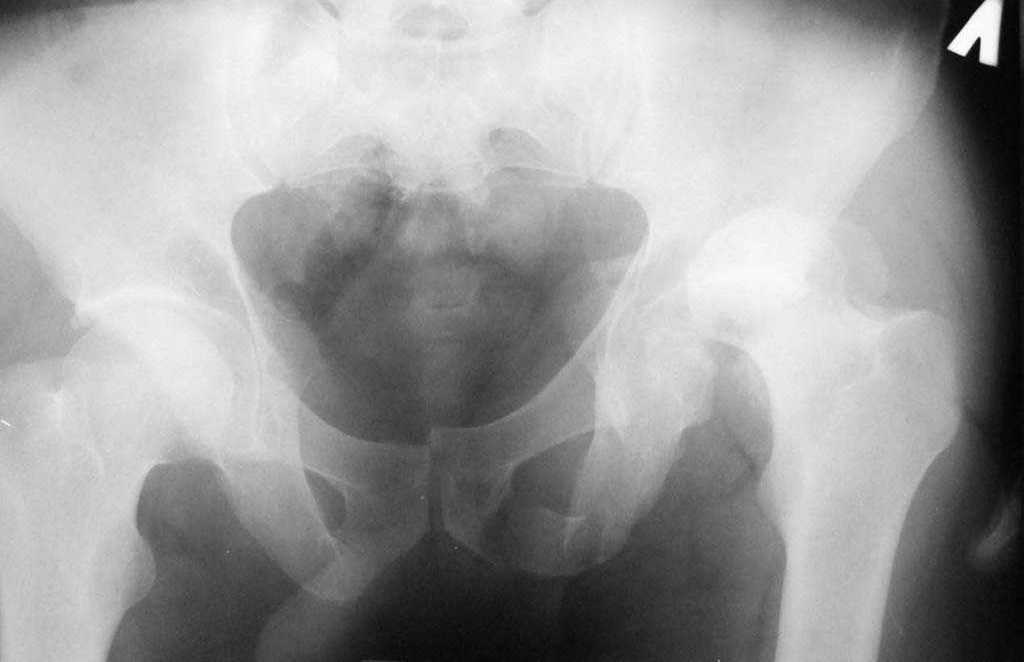

Дополнение, минимальный набор необходимых прекций, необходимых для лечения повреждений вертлужной впадины

Фас. Inlet

Подвздошная Запирательная